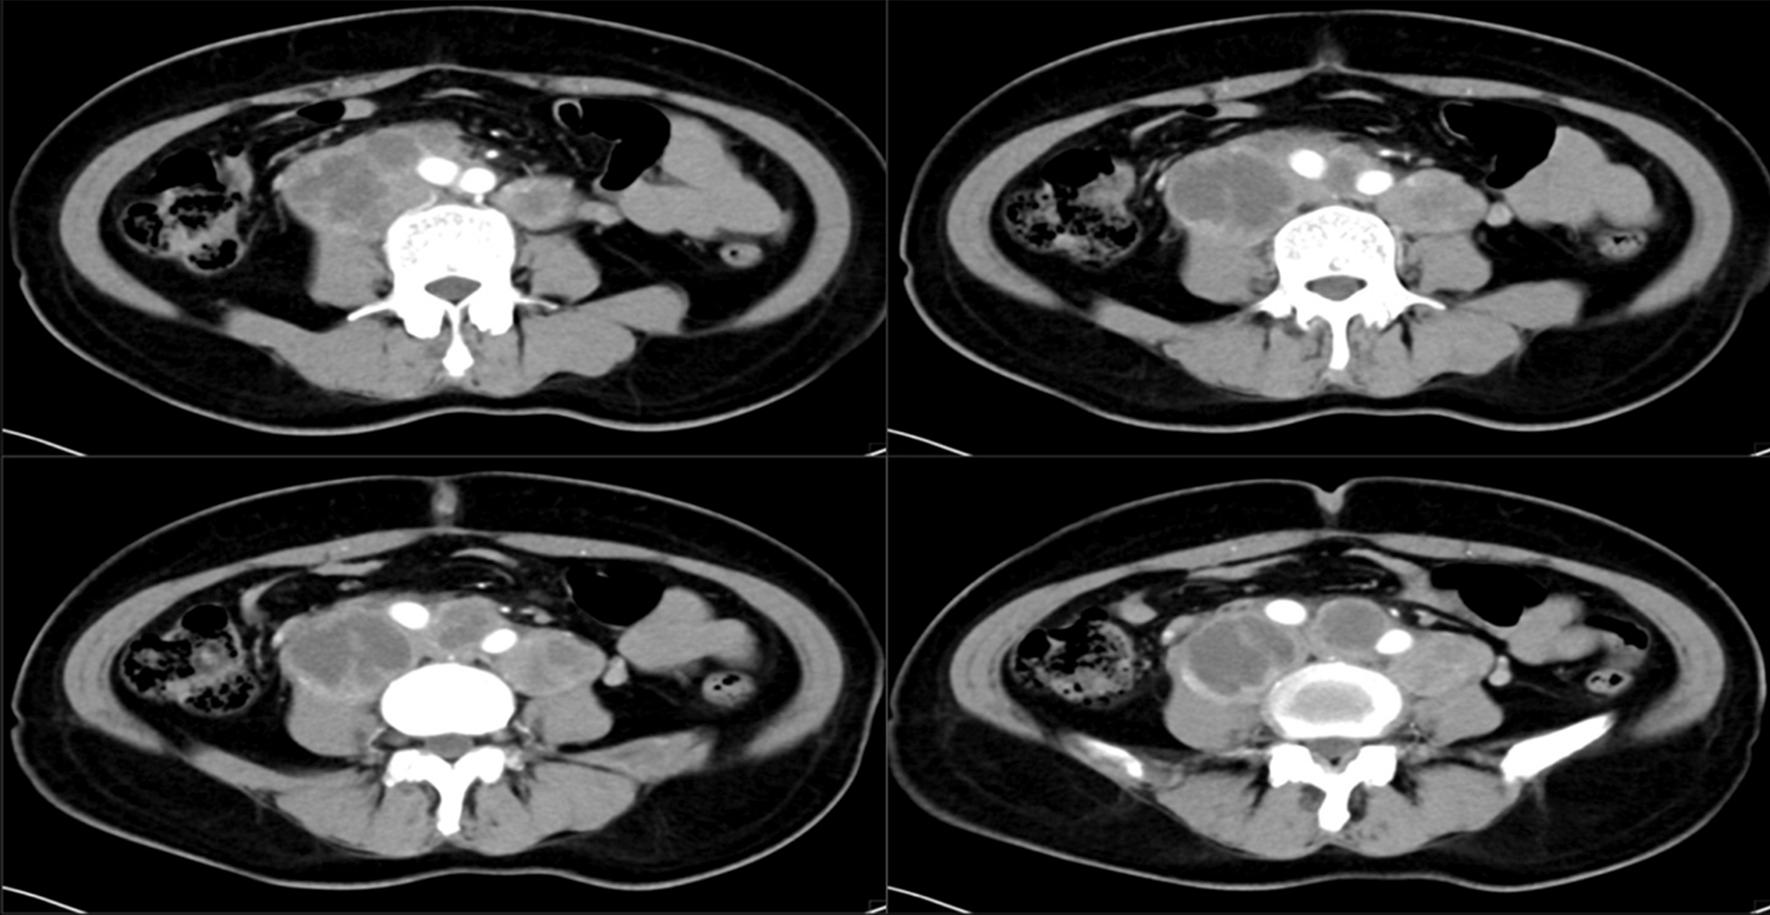

A 54-year-old female patient was first admitted to the hospital in January 2018 due to "irregular vaginal bleeding over 3 months". CT showed a mass in the uterine cavity, and several swollen lymph nodes in the retroperitoneum and pelvic cavity. The initial diagnosis was an endometrial malignant tumor. We performed radical endometrial cancer surgery with parallel resection of inferior vena cava, abdominal aorta, bilateral common iliac arteries, bilateral external iliac arteries, and artificial vessel replacement, which was successful, with good postoperative recovery and no lesion progression at 3 years postoperative follow-up.